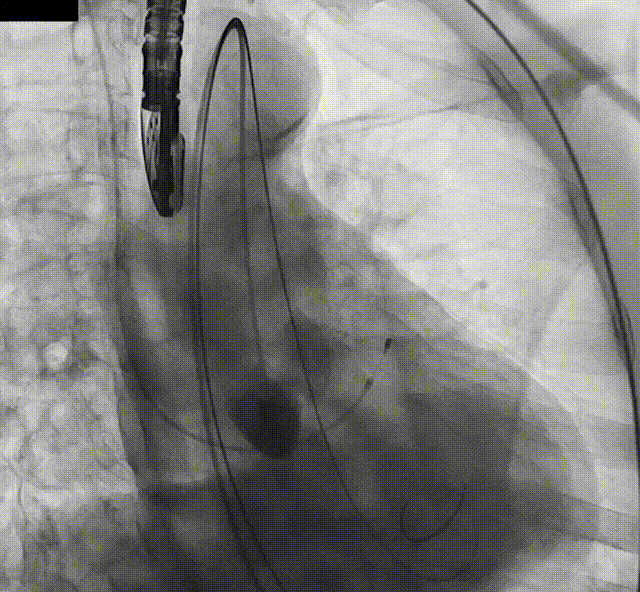

TaurusElite®轻松过弓

精准定位

瓣膜快速释放工作位

反复调整释放深度,最终精准定位零度释放位点,起搏180次/分,TaurusElite®AV29mm瓣膜快速释放了四分之三。